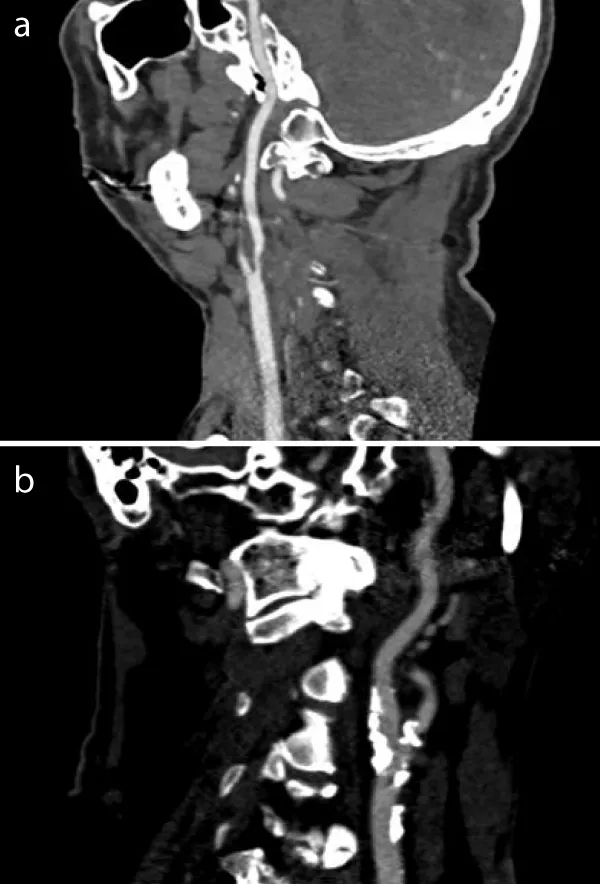

CT-Angiography findings

The CT-angiography of a patient with soft plaque shows bilateral high-grade internal carotid stenosis due to artheromatous plaque. Compared to the vascular environment, hypodense concentric plaque is shown intraluminally. The lumen itself contrasts hyperdensely calcified plaque is not detectable (Figure 1a).

The CT angiography of a patient with hard plaque also shows high-grade internal carotid stenosis due to calcifying plaques. There is hardly any evidence of hypodense internal plaques. A small hyperdensely contrasted lumen with extensive, bizarre, fissured calcifications, sometimes with adjacent hardening artefacts, is shown (Figure 1b).

Figure 1: a: CT-Angiographie finding from a patient with soft plaque: intraluminally hypodensic concentric plaque without calcified areas. b: CT-Angiographie finding from a patient with hard plaque: high-grade internal carotid stenosis with extensive, bizarrely fissured calcifications.